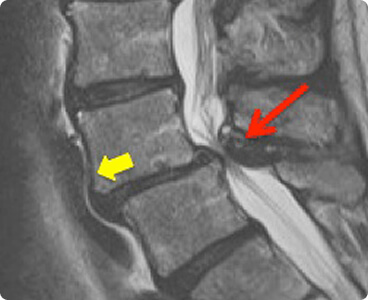

While XRays can determine whether a compression fracture exists, an MRI can determine whether it is new (acute) or chronic (old).   A compression fracture that has fluid and swelling in it is considered new and may be amenable to effective minimally invasive, interventional treatment, such as a kyphoplasty and vertebroplasty.

A compression fracture that does not have fluid is thought to be old and is usually treated conservatively with analgesics.  If the fracture is felt to be unstable, the spinal cord may be at risk of damage and surgical treatment is required.